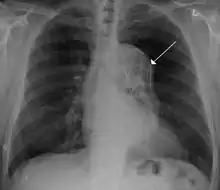

A thoracic aortic aneurysm is an aortic aneurysm that presents primarily in the thorax.

A thoracic aortic aneurysm is the "ballooning" of the upper aspect of the aorta, above the diaphragm. Untreated or unrecognized they can be fatal due to dissection or "popping" of the aneurysm leading to nearly instant death. Thoracic aneurysms are less common than an abdominal aortic aneurysm.[2] However, a syphilitic aneurysm is more likely to be a thoracic aortic aneurysm than an abdominal aortic aneurysm. This condition is commonly treated via a specialized multidisciplinary approach with both vascular surgeons and cardiac surgeons.

The principal causes of death due to thoracic aneurysmal disease are dissection and rupture. Once rupture occurs, the mortality rate is 50–80%. Most deaths in patients with Marfan syndrome are the result of aortic disease.